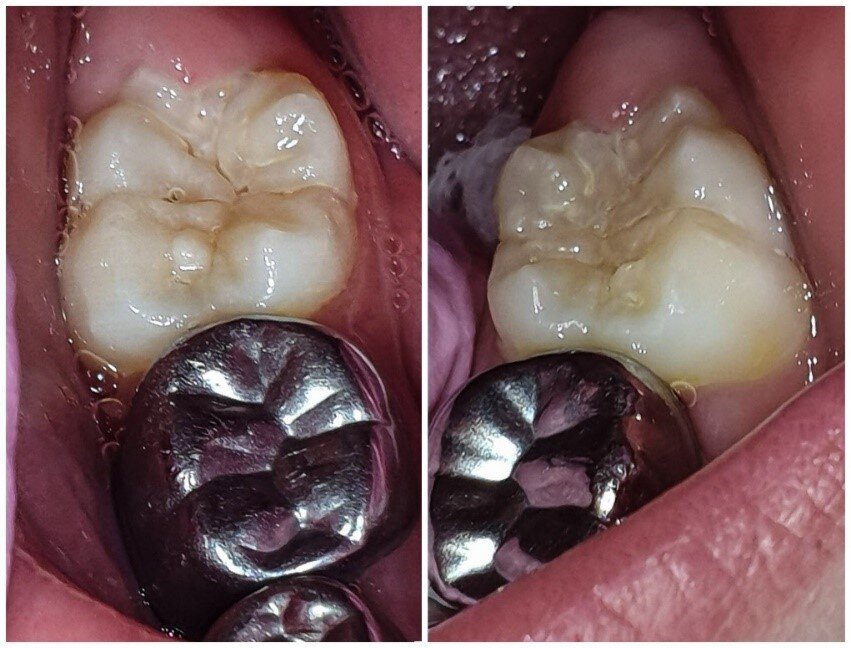

Afbeelding 4a: Kleurfoto’s op de leeftijd van 6 jaar, juli 2018. Alle cariëslaesies in de bovenkaak zijn arrested, in de 55, 64 en 65 met ondersteuning van SDF. Laesies die tijdens het aanbrengen arrested waren, zijn niet verkleurd.

Afbeelding 4b: Kleurfoto’s op de leeftijd van 6 jaar, juli 2018. Alle cariëslaesies in de bovenkaak zijn arrested, in de 55, 64 en 65 met ondersteuning van SDF. Laesies die tijdens het aanbrengen arrested waren, zijn niet verkleurd.

Jenny is 6 jaar. Er worden röntgenopnames en kleurenfoto’s gemaakt (Afb. 3 en 4). Op de röntgenfoto’s lijken de bovenmolaren ernstig aangetast, maar ze zijn hard en inactief. De niet-gerestaureerde bovenmolaren en kronen met gerestaureerde ondermolaren zijn vrij van ontsteking. Jenny kwam voor mondonderzoek om de 4-6 mnd.

Afbeelding 5a: Kleurfoto’s op de leeftijd van 7 jaar, juli 2019. Alle cariëslaesies in de bovenkaak zijn arrested, hard en glanzend, goed bereikbaar voor het poetsen. De mondhygiëne is goed. De eerste blijvende molaren breken door.

Afbeelding 5b: Kleurfoto’s op de leeftijd van 7 jaar, juli 2019. Alle cariëslaesies in de bovenkaak zijn arrested, hard en glanzend, goed bereikbaar voor het poetsen. De mondhygiëne is goed. De eerste blijvende molaren breken door.